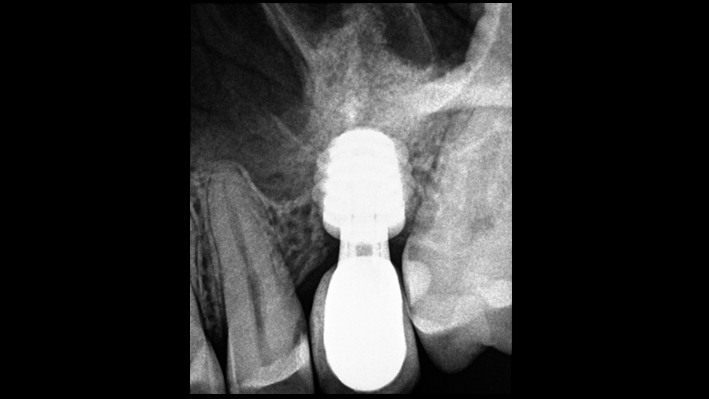

Clinical case: # 46 implant placement & GBR using i-Gen membrane for significant vertical resorption & mixed bone defect

- Courtesy of Dr. Iulian Filipov, Romania -

AnyRidge, mandibular posterior, i-Gen, resorption, bone defect, bone regeneration, space management, #46, GBR, Dr. Iulian Filipov